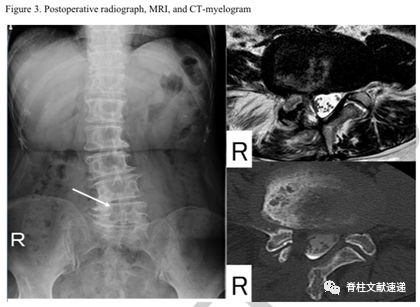

术前资料